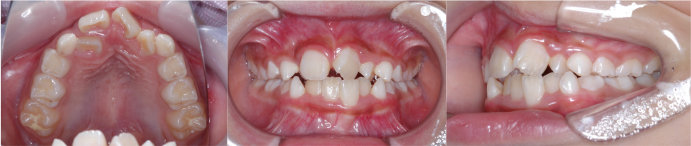

| Case3 |

| 受け口 |

| <治療前> |

| <治療後> |

| 主訴 |

上の歯がねじれている |

| 診断名 |

叢生を伴う反対咬合 |

| 年齢 |

10歳 |

| 使用装置 |

マルチブラケット装置 |

| 抜歯部位 |

永久歯の抜歯は無し |

| 治療期間 |

3年6か月 |

| 治療費概算 |

検査・診断料:5万円+税 装置・技術料:25万円+税 おおよそ1か月ごとの処置・管理料:5,000円+税 保定装置料:5万円+税 |

| リスク・副作用 |

う蝕 |